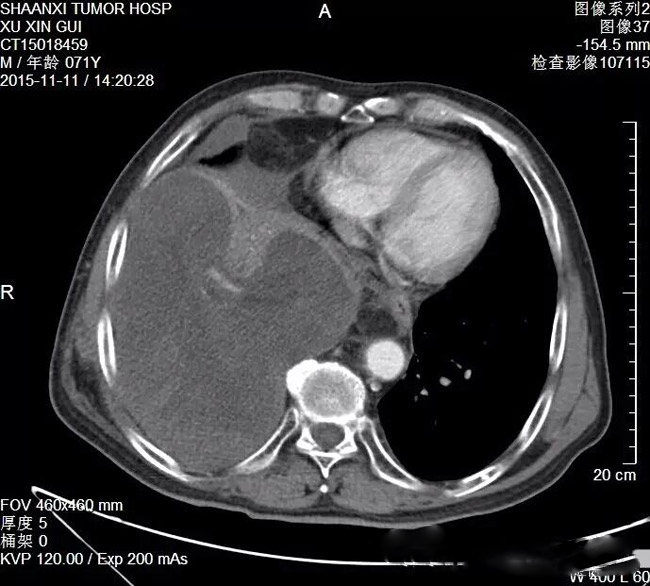

近日,一位来自安康的71岁男性患者,因右侧胸腔脂肪肉瘤术后2年复发,致胸痛、气短难忍,走访省内多家医院后,最终选择了素股 胸外科。

胸外科主任雷光焰教授仔细分析后认为,患者右侧胸腔复发肿瘤体积巨大,占据右侧胸腔三分之二,压迫右肺中叶及下叶,致使完全肺不张,唯有手术可以缓解症状,挽救患者生命。经与患者家属充分沟通、术前精心准备后,于2015年11月17日由雷光焰主任带领胸外二病区的手术团队,在克服了肿瘤巨大、手术视野小、术中出血多、胸腔广泛粘连、与周围组织器官界限不清等多重困难后,最终成功完整切除肿瘤。手术摘除的肿瘤重达6斤,最长径超过30cm,这么大的肿瘤实属罕见。术中同时将已毁损的右肺中下叶一并切除,并给予顺铂胸腔热灌注化疗,减少术后肿瘤复发机会。术后患者顺利出院。